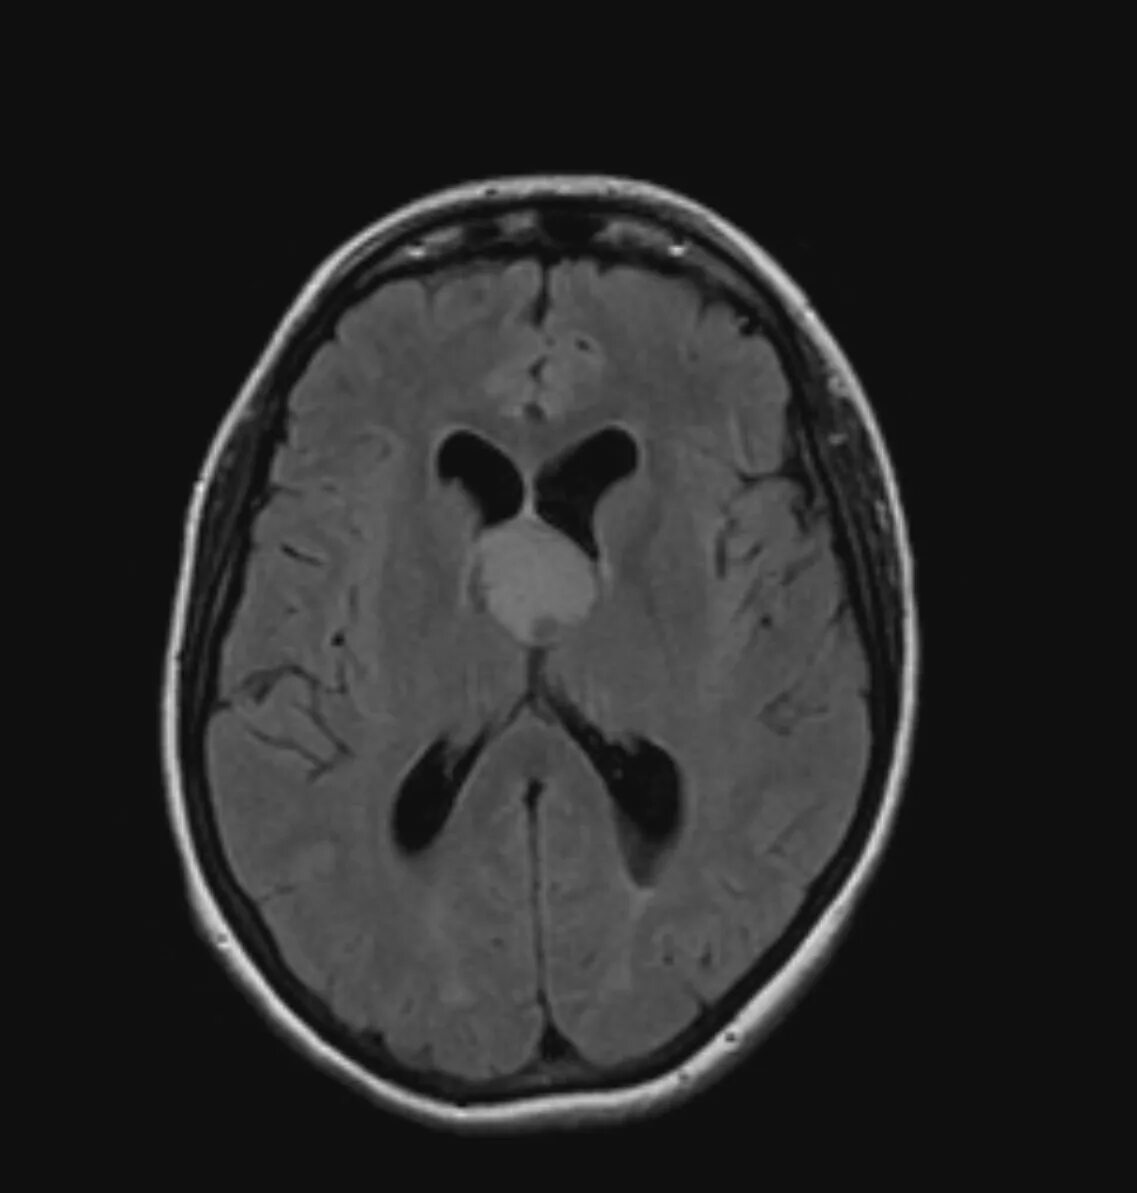

Расширение субарахноидального пространства что это значит